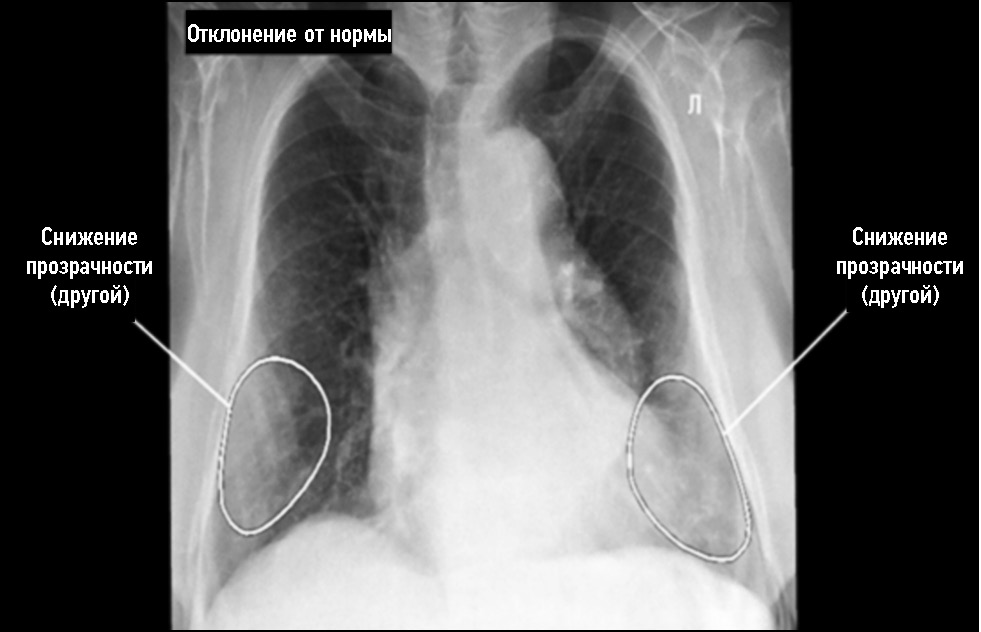

Стоит отметить вероятность наличия теней дополнительных мягкотканных, в том числе кожных образований, уплотнений и сосков молочных желёз, проецирующихся на рентгеновское изображение лёгких, которые могут быть ошибочно интерпретированы ПО на основе ТИИ как лёгочные образования, и требующих пересмотра врачом [22, 23]. В рамках данного исследования был выявлен один ложноположительный случай срабатывания ПО на основе ТИИ, связанный с выраженной подкожно-жировой клетчаткой (рис. 5), а также один случай, когда ИИ-сервис принял тень соска за лёгочный узел (рис. 6).

Рис. 5. Ложноположительный случай срабатывания программного обеспечения на основе технологий искусственного интеллекта, связанный с выраженной подкожно-жировой клетчаткой.